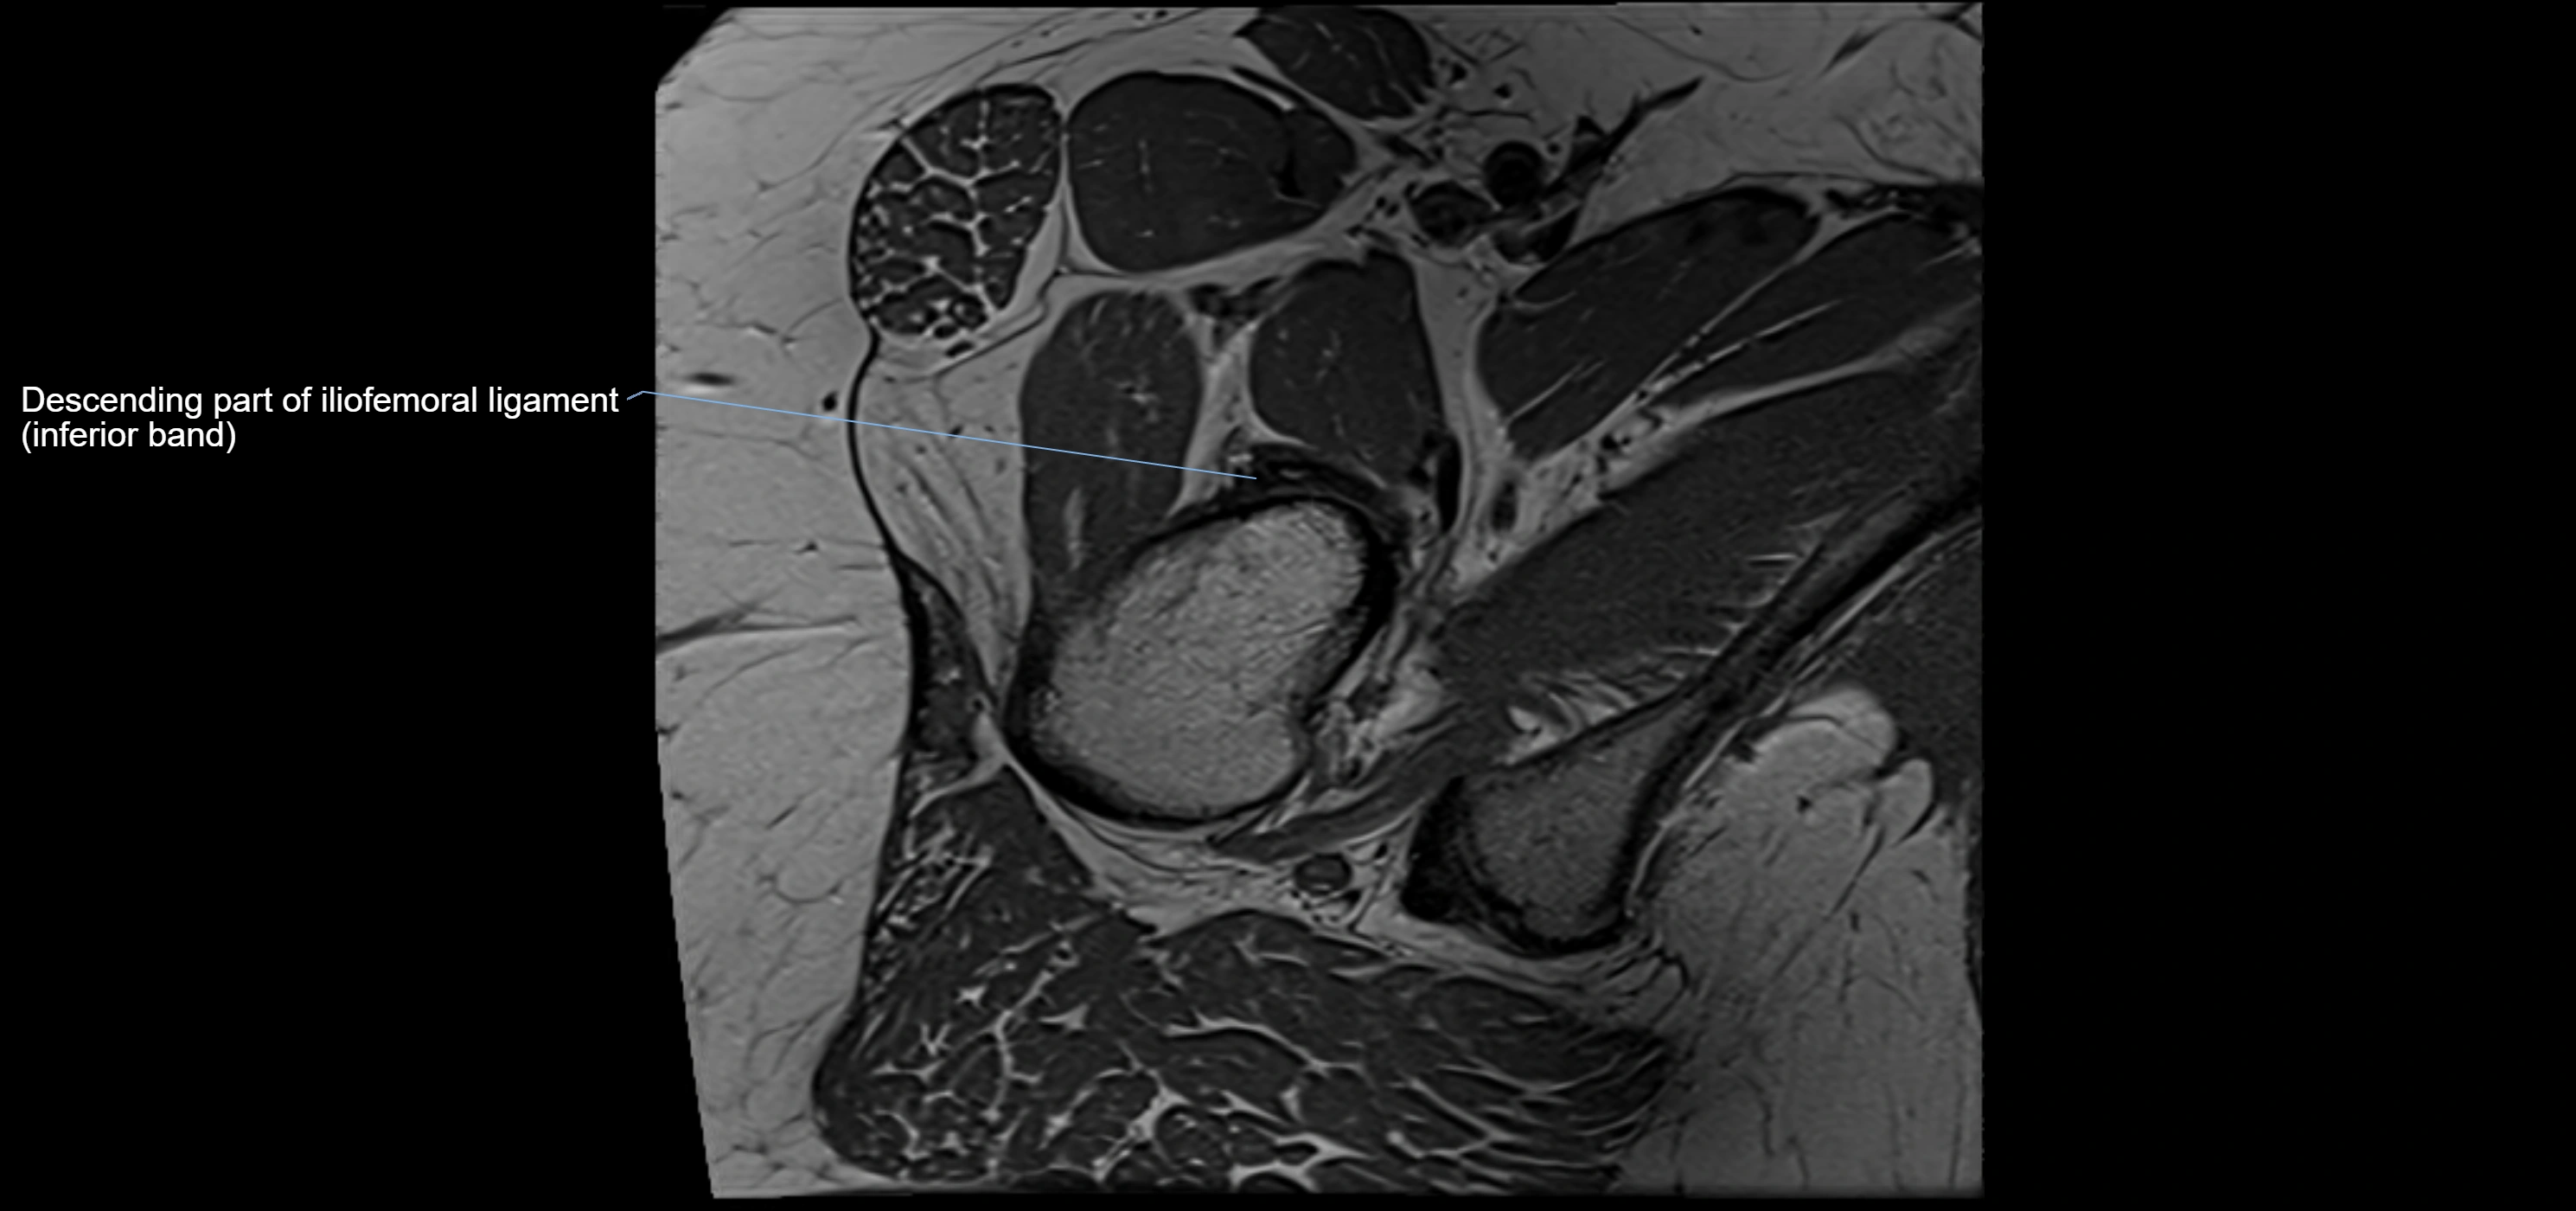

MRI image

image